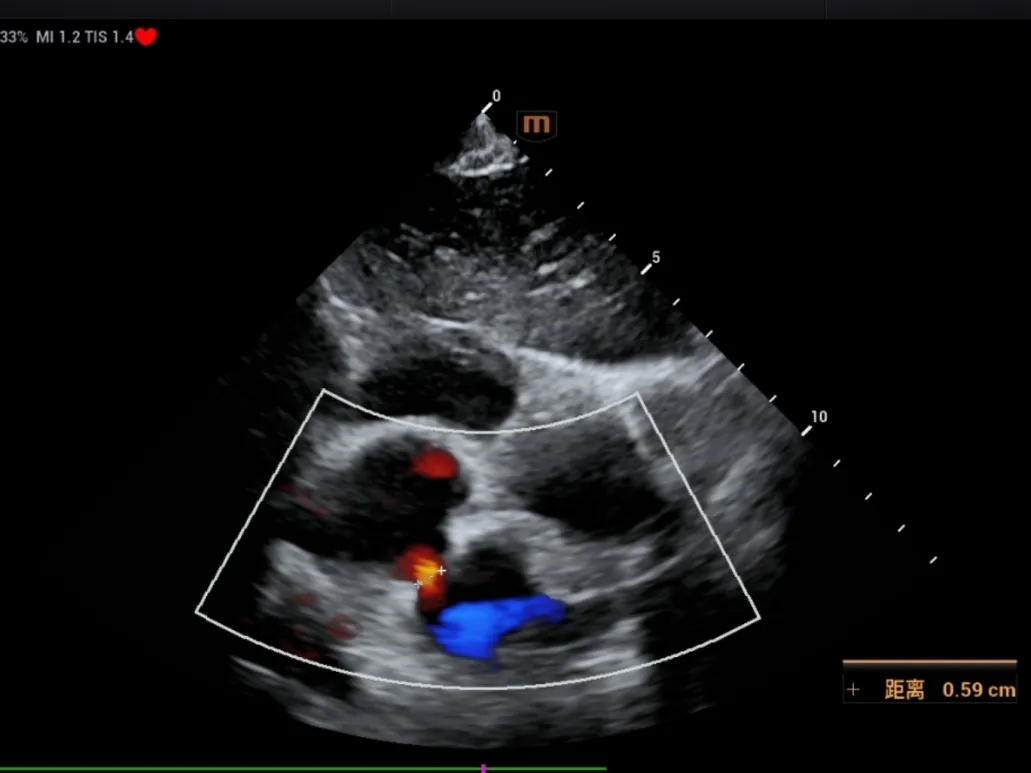

释放后评估

超声下可见封堵器形态良好,多普勒显示无残余分流,封堵成功。

出院前评估

超声所见:1、各房室腔内径正常。大动脉内径及位置关系正常。2、室间隔及左室后壁厚度及运动幅度正常。房间隔中部见封堵器回声,位置良好,CDFI:房水平未见明显分流。室间隔连续。3、CDFI示三尖瓣见小反流束;余瓣膜形态回声及启闭未见明显异常。4、心包厚度正常,心包腔内未见液性暗区。5、心功能测值正常。

超声提示:房间隔封堵器术后,封堵器位置正常。

出院前患儿心功能指标正常,肺动脉压恢复正常,二尖瓣反流消失,三尖瓣反流由术前少量转为轻微。